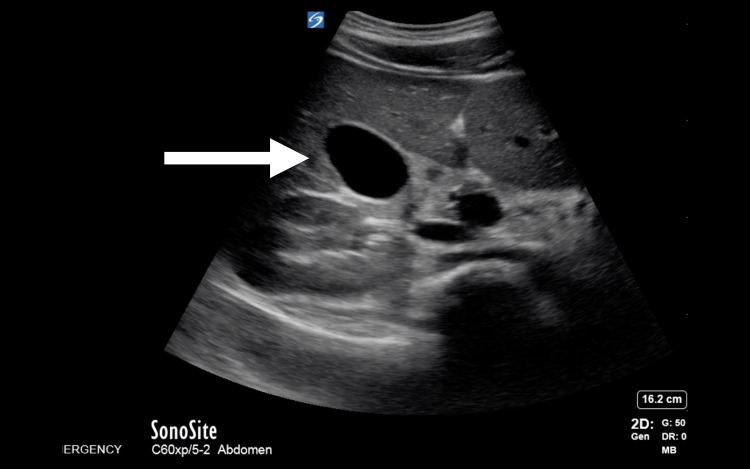

Abstract Image